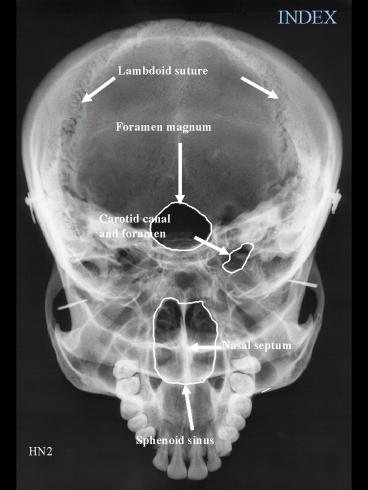

INDEX

Lambdoid suture

Foramen magnum

Carotid canal and foramen

Nasal septum

Sphenoid sinus